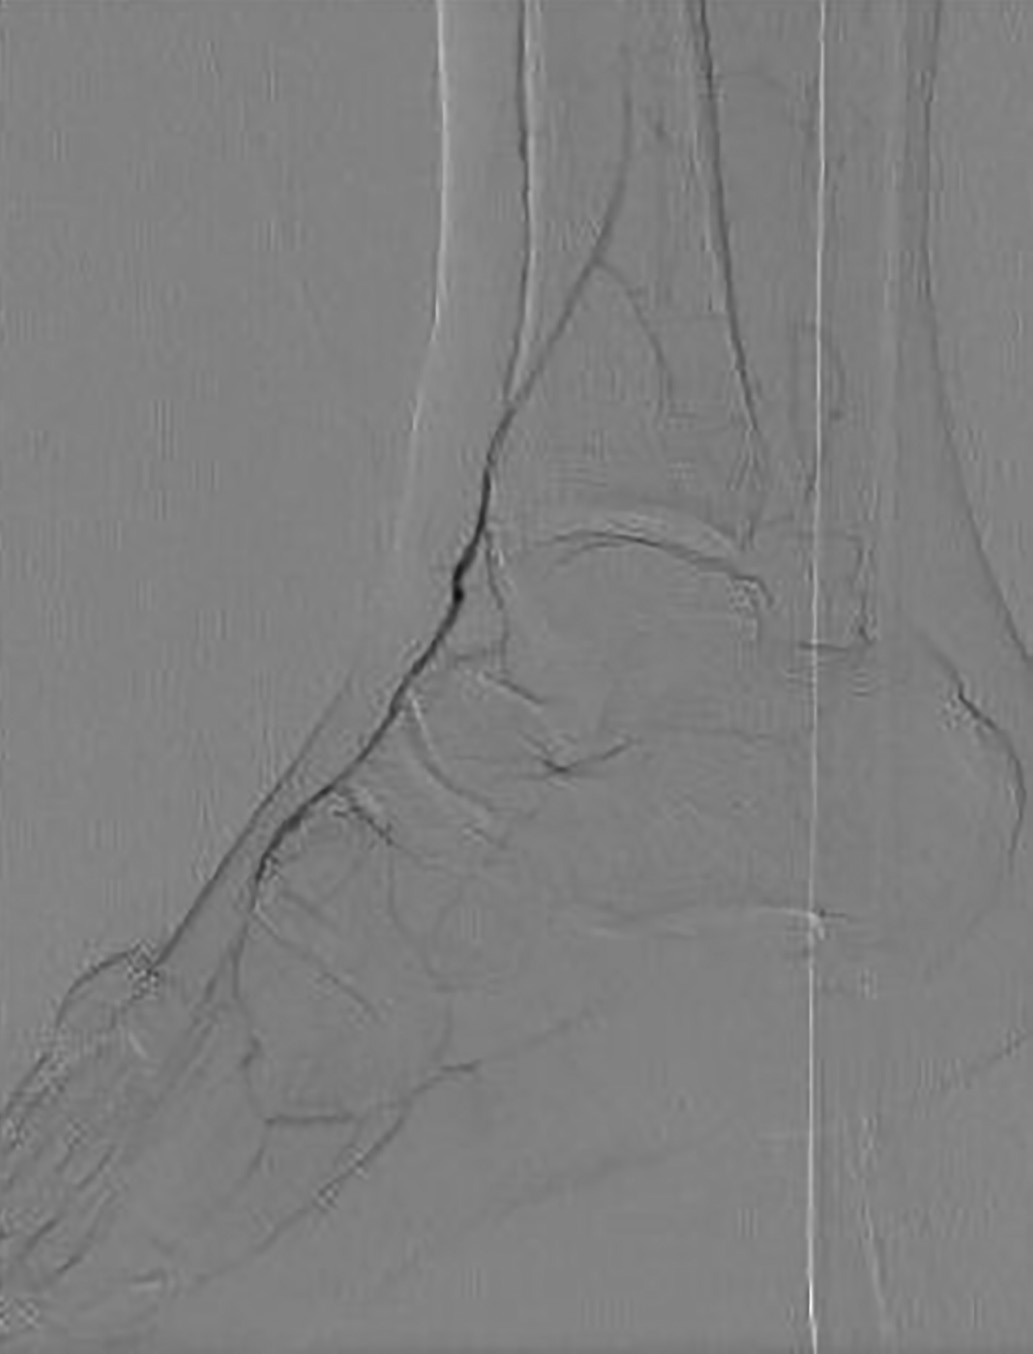

УЗДС артерий нижних конечностей

Заключение: атеросклероз магистральных артерий нижних конечностей. Эхографические признаки склероза Менкеберга (рис. 2а).

Справа: общая подвздошная и наружная подвздошная артерии (ОПА и НПА) — проходимы, стеноз 20–25% за счет мелких кальцинированных атеросклеротических бляшек (АСБ) по передней и задней стенкам. Общая бедренная артерия и глубокая артерия бедра (ОБА и ГАБ) — проходимы, перед бифуркацией ОБА и в устье ГАБ — циркулярная гиперэхогенная АСБ, стеноз 30%. Поверхностная бедренная артерия (ПБА) — в устье циркулярная гиперэхогенная АСБ, стеноз 20%, на протяжении по передней и задней стенкам диффузные АСБ, стеноз 30–40%. Стеноз подколенной артерии и тибиоперонеального ствола (ПкА и ТПС) до 30%. Задняя большеберцовая артерия и малоберцовая артерия (ЗББА и МБА) — визуализируется диффузное относительно равномерное повышение эхогенности сосудистой стенки в сочетании с утратой дифференцировки на слои. На всем протяжении — полисегментарное циркулярное обызвествление сосудистой стенки. По передней и задней стенкам лоцируются диффузные гиперэхогенные кальцинированные включения, мелкие кальцинированные АСБ, стенозы в верхней трети голени 50%, в средней и нижней трети голени — локальные стенозы до 80–90%. ЛСК по ЗББА 51 см/с в н/3 голени (рис. 2б). Передняя большеберцовая артерия (ПББА) — в устье и частично в верхней трети голени проходима, дистальнее ствол артерии не определяется (гипоплазия). Тыльная артерия стопы (ТАС) фрагментарно окклюзирована, кровоток коллатеральный, компенсированный, ЛСК — 88,6 см/с (рис. 2в). Латеральная подошвенная артерия (ЛПА) фрагментарно окклюзирована, кровоток коллатеральный, компенсированный, ЛСК — 43 см/с (рис. 2г). Кровоток по мелким артериям стоп: кровоток в 3-4-м межфаланговых промежутках (в области раны) по тыльным плюсневым (ТПА) и подошвенным плюсневым (ППА) артериям коллатеральный декомпенсированный, ЛСК — 21–22 и 14–15 см/с (рис. 2 д-е).

Рисунок 2. Ультразвуковое дуплексное сканирование

артерий нижних конечностей при поступлении.

а — выраженный кальциноз сосудистой стенки задней большеберцовой артерии правой нижней конечности. В-режим;

б — магистрально-измененный кровоток по задней большеберцовой артерии, линейная скорость кровотока — 51 см/с. Режим цветового допплеровского картирования, дополненный допплерографией;

в — коллатеральный компенсированный кровоток по тыльной артерии стопы, линейная скорость кровотока — 88,6 см/с. Режим допплерографии;

г — коллатеральный компенсированный кровоток по латеральной подошвенной артерии, линейная скорость кровотока — 43 см/с. Режим цветового допплеровского картирования, дополненный допплерографией;

д — коллатеральный декомпенсированный кровоток по тыльным плюсневым артериям в 4-м плюсневом промежутке, линейная скорость кровотока — 14–15 см/с. Режим цветового допплеровского картирования, дополненный допплерографией;

е — коллатеральный декомпенсированный кровоток по подошвенным плюсневым артериям в 4-м плюсневом промежутке, линейная скорость кровотока — 21–22 см/с. Режим цветового допплеровского картирования, дополненный допплерографией.

Таким образом, прицельное УЗДС в околораневой зоне позволило выявить значимое нарушение кровотока у нашего больного в зоне интереса. Полученные выводы необходимо подтвердить методами оценки перфузии мягких тканей стопы.